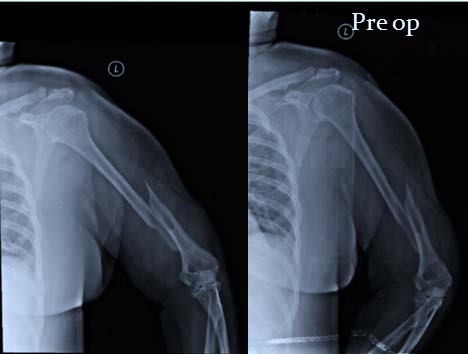

It was a Prospective study conducted at Sri Ramachandra Medical College & Research Institute, Chennai during April 2015 and August 2017. The study consisted patients of closed injury with distal humerus extra-articular fractures in skeletally mature patients, and excluded intra-articular fractures of elbow, paediatric age group, proximal humerus fractures, previouslytreated or operated with other internal fixation methods/devices but failed, open injuries, and patients having a pre-operative neuro-vascular deficit. Preoperatively patients were evaluated clinically, radiologically and the diagnosis was established and classified using the AO/ASIF Classification. Twenty (20) patients of distal humerus extra-articular fractures were at hand of which Nineteen (19) were available for final assessment. Our follow-up period ranges from 6 weeks to 1 year. The Implant used was LCP Extra-articular Distal Humerus Plate, which is anatomically shaped, and angular stable fixation system for extra-articular fractures fixation of the distal humerus. The LCP head is tapered to minimize soft tissue irritation; five distal locking holes accept 3.5 mm locking screws, all head holes are angled medially to maximize screw purchase in bone, two most distal holes are angled toward the capitulum, and trochlea. whereas in the Plate shaft Combi holes combine a dynamic compression unit (DCU) hole with a locking screw hole, providing the flexibility of axial compression, and locking capability throughout the plate shaft, Limited-contact design, Available with 4, 6, 8, 10, 12 or 14 elongated Combi holes to accommodate distal humerus fractures with shaft involvement (figure 1) The patient is nursed in absolute aseptic conditions in the postoperative ward with the limb in hanging position by pillow cover elevation. Parental antibiotics were continued for the first two days followed by oral antibiotics for the next three days. Pain management was done with intra-venous analgesic, and was removed on the 2 nd post-operative day. There after oral analgesics were given. Drain is removed at the end of 48 hrs. As soon as pain subsides, Rehabilitation Protocol is started with physiotherapy. The Active elbow flexion-extension and supination-pronation exercises with the aim of maximum ranges of motion; as soon as possible but as tolerated by the patients. The patient was advised to continue exercises here or any other convenient centre. Sutures were removed during 12 th to 14 th post-operative day. After the surgery, functional evaluation was done with DASH, MAYO and VAS score (figure 3, 4, and 5) at six weeks, three months, six months, and one year.

Road traffic accident was the major cause of injury 63.2%; followed by slip and fall 26.3%, one case of pathological (5.3%), and sports injury (5.3%) each. The mean metaphyseal-diaphyseal angle was 86.21° (SD3.441°, normal 82-84°), the mean humeralulnar angle was 14.63° (SD 2.338°, normal 17.8° valgus), and the mean shaft-condylar angle was 39.84° (SD 1.500°, normal 40°). The anterior humeral line passed through 50.00 % (SD 1.491 %) of the capitellar width (normal, middle third). Flexion movement was good throughout followup, and was statistically significant from 6 weeks to 3 month; 6 week to 6 month, 6 week to 1 year, 3 month to 6 month, 3 month, 1 year respectively, and was not significant at 6 month -1 year. That means patient had almost recovered by 6 week follow-up, little improvement was there up to 1 year from initial time of follow-up. When compared with last 6 month of followup there was no further improvement possible as patient had already achieved there anatomical range of movement (Figure 10). The extension was significantly improved when the patient came for follow-up at 6 weeks, and mean extension was 3.68 ± 6 degrees. Later at 3, 6 months and 1 year where almost normal extension was possible in all cases except complicated cases; thus there was no scope of further extension at latter visits, and test were insignificant statistically (Figure 11). Supination was not statistically significant at any follow-ups. That means the patient had recovered to an anatomical range of movement by 6 week of followup, and there was no further improvement possible (Figure 12). Pronation was not statistically significant at any follow-ups. That means the patient had recovered to the anatomical range of movement by 6 week follow-up, and there was no further improvement possible (Figure 13). Dash score was decreasing over one year. The Score was compared at 6 weeks to 3 month, 6 month, and 1 year respectively; at 3 month to 6 month, 1 year respectively, and at 6 month to 1 year. All intervals were statistically significant (p<0.05) indicating improvement in patients daily activities to normal over 1 year (Figure 14). Mayo score was increasing over a period of one year. The score was compared; At 6 weeks to 3 month, 6 month, 1 year respectively; 3 month to 1 year;, and at 6 month to 1 year. All interval were statistically significant (p <0.05) except at 3 month -6 month period where it was statistically insignificant due to one case of malunion, and implant failure. Otherwise, all patients recovered to almost normal over 1 year (Figure 15). VAS score was minimal at 6 weeks, and was decreasing at later follow-ups. It was found to be significant at 6 weeks i.e. patient were relived of pain by 6 weeks to 3 months. Later it was marginally significant at 6 months but it was due to case of implant failure that came up with aggrieved pain complaints. Otherwise; in other patient's it was insignificant after 3 months as patients were relived of pain, and there was no scope for any further pain relief (Figure 16).